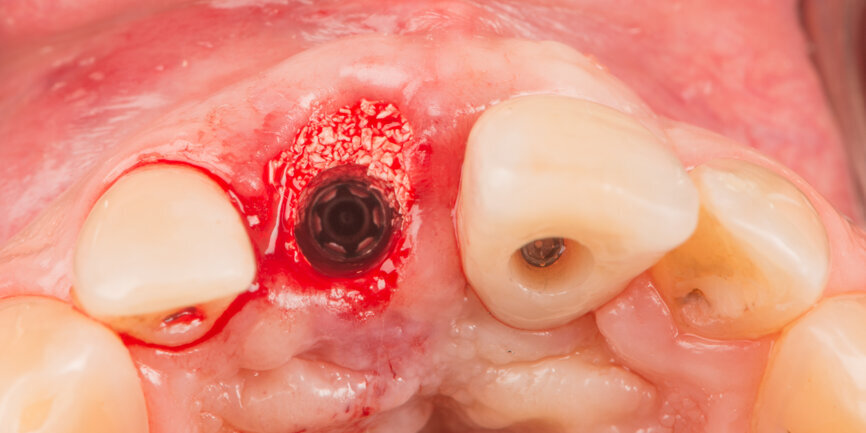

Tooth #11 was extracted atraumatically without raising a flap or performing an osteotomy (Fig. 4). The extraction socket was meticulously cleaned and rinsed with Betadine. The drilling sequence included 2.2, 2.8, 3.2 and 3.7 mm drills (Fig.5). The implant was placed with a final torque of 80 N cm (Figs. 6 & 7). In its final position, the implant platform lay 4 mm below the ideal gingival margin (at the same level of the adjacent implant platform; Fig.8).

A Regular Base (RB) titanium temporary abutment for a crown was placed and a laboratory-made shell was positioned without interference with the temporary abutment (Fig. 9). The surgical site was protected with a small piece of rubber dam (Fig. 10), and the abutment was connected to the shell with a dual-curing luting composite (Fig. 11). The development of a proper emergence profile will be done extra-orally (Fig. 12) to produce the screw-retained temporary crown.

Before placing the provisional crown, the gap between the implant and the buccal plate was filled with a particulate xenograft material (cerabone, botiss biomaterials). The graft was packed up to the gingival margin according to the dual-zone principle described by Chu et al. (Fig. 13).[7] The screw-retained temporary crown was then torqued to 35 N cm (Fig. 14).